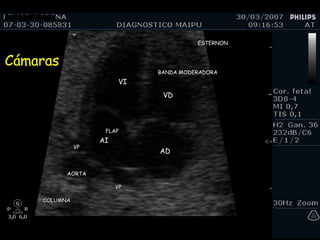

Cámaras COLUMNA AORTA ESTERNON VP VP BANDA MODERADORA FLAP VI VD AI AD